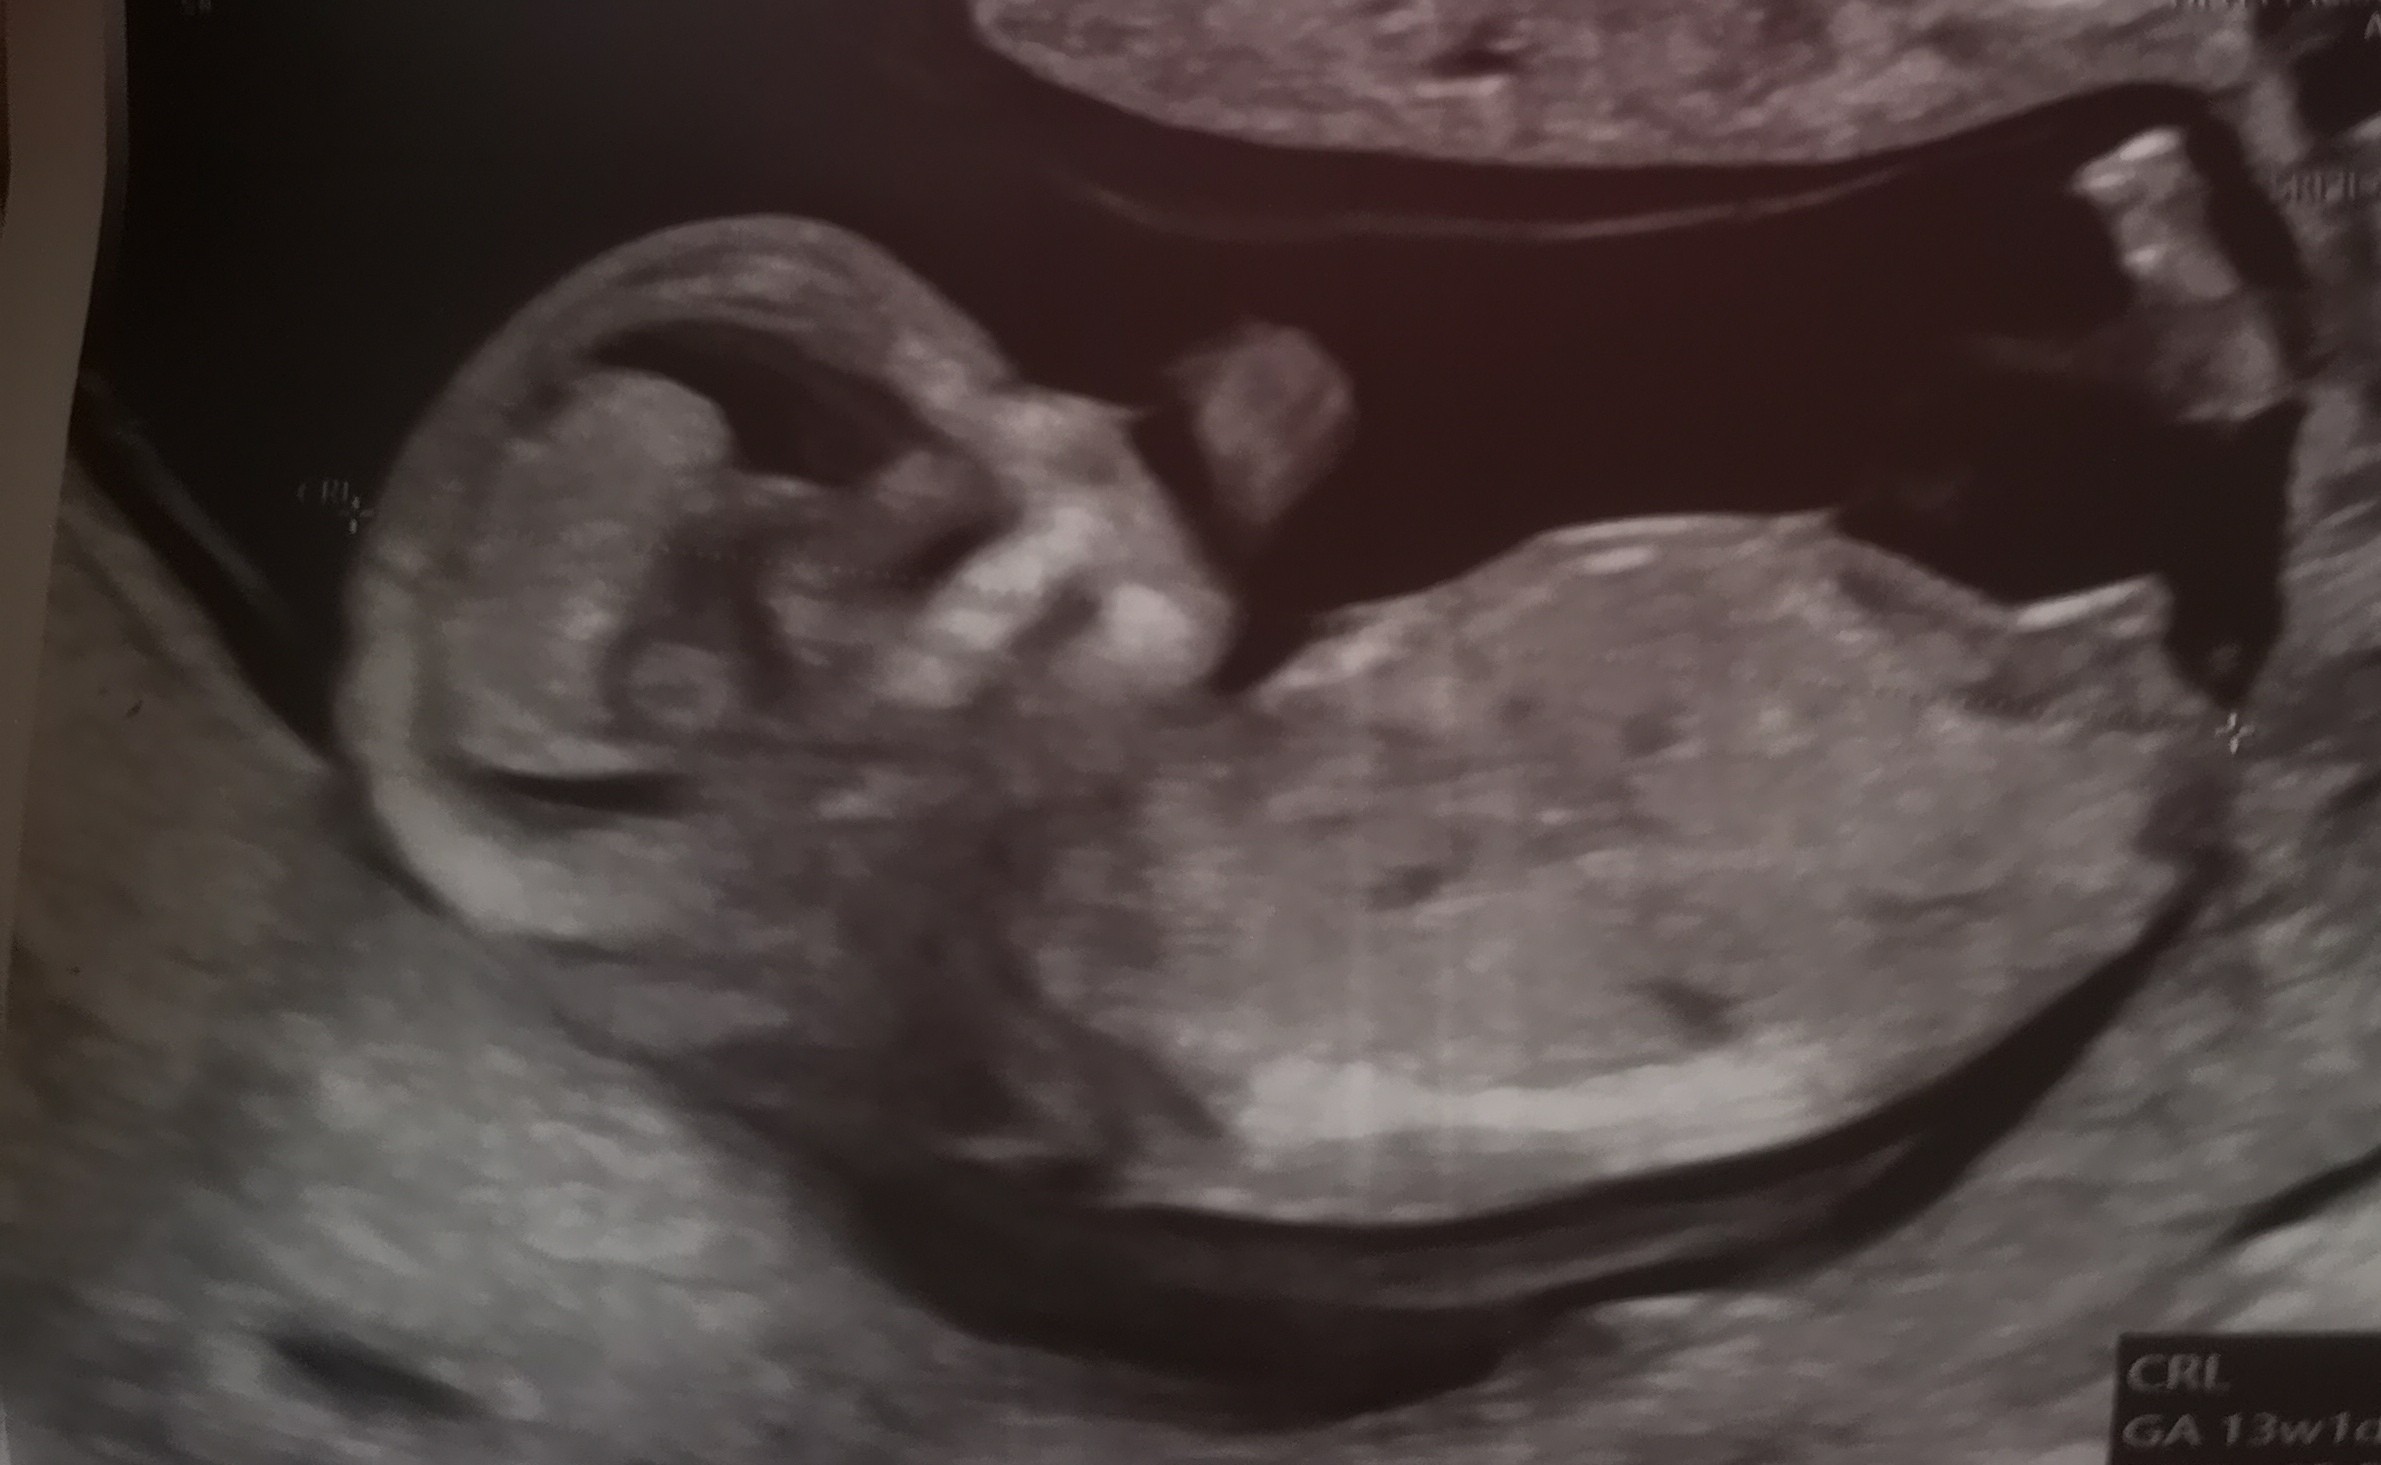

Cześć dziewczyny,

Dziewczynka czy chłopiec?

IMG_20240207_171045.jpg

IMG_20240207_171028.jpg